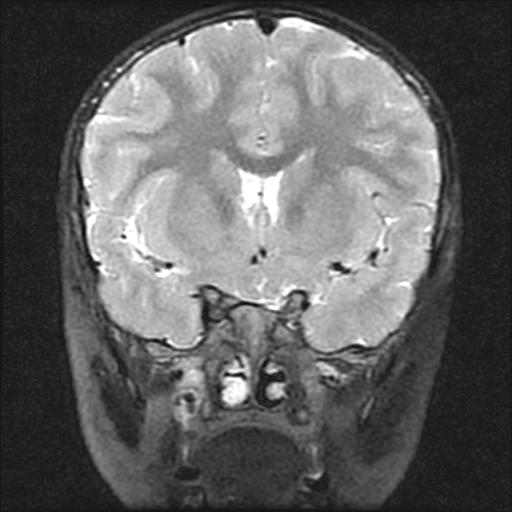

6岁小儿,左侧视神经瘤术后。现左侧视力减退。